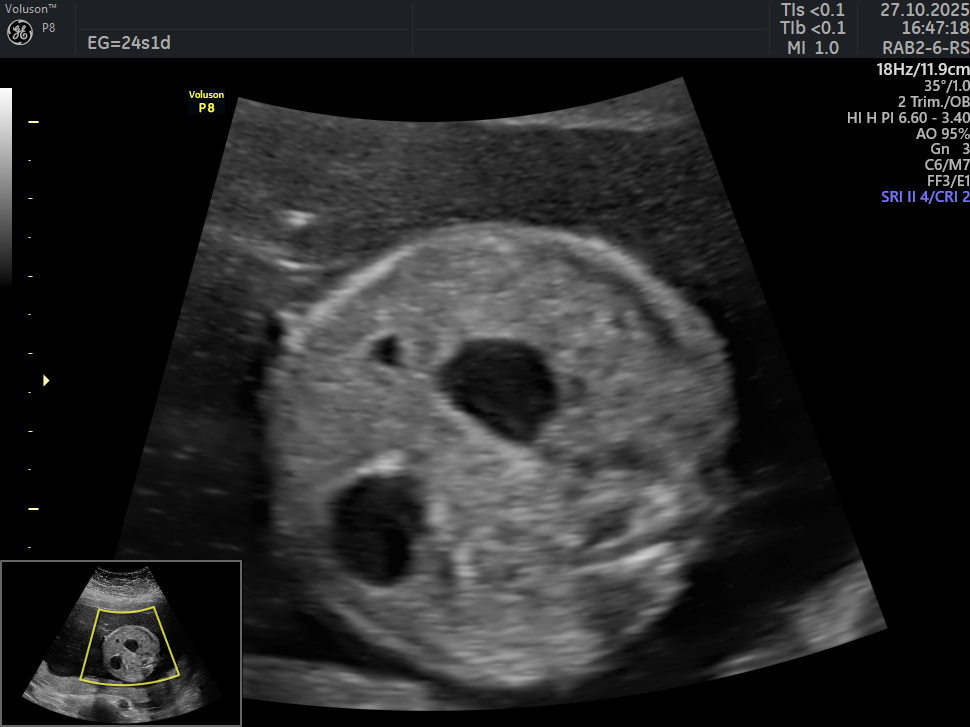

Se presenta el caso de una paciente de 39 años de edad, primigesta, sin antecedentes personales ni familiares de relevancia. La paciente adjunta el estudio de screening de aneuploidías de la semana 11-14, que arroja bajo riesgo. Las imágenes que se presentan a continuación corresponden al estudio morfológico fetal realizado en la semana 24. Seleccione la opción correcta : A. Se visualiza cámara gástrica dilatada, conectada con una imagen quística anecogénica, de probable origen duodenal (Signo de la doble burbuja). B. La anatomía es de apariencia normal para la edad gestacional. C. Los hallazgos podrían corresponder a una probable atresia esofágica. D. Los hallazgos podrían corresponder a una dilatación quística del conducto biliar.